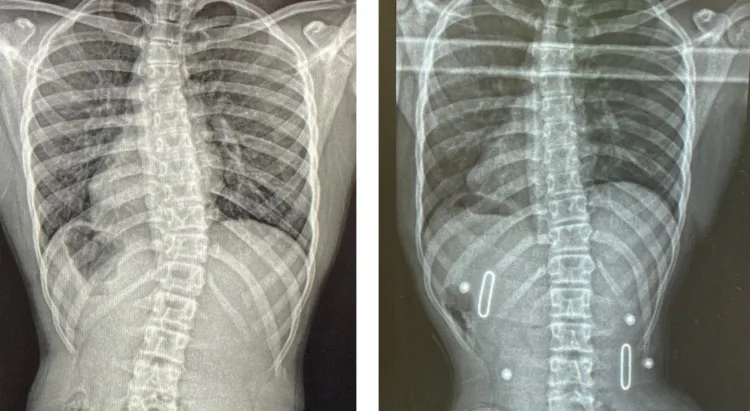

الأشعة الدورية: لتحديد زاوية الانحناء ومتابعة أي تغير.

الحزام التصحيحي عند الحاجة: في بعض الحالات، يساعد على تقويم العمود الفقري ومنع زيادة الانحناء.

الانحناءات الصغيرة في العمود الفقري بين 10 و25 درجة تمثل فرصة ذهبية للتدخل المبكر قبل أن تصبح التغيرات الهيكلية أكثر صعوبة في التصحيح. الدراسات الحديثة تؤكد أن أفضل النتائج تتحقق عند بدء العلاج في هذه المرحلة، سواء من خلال العلاج الطبيعي المخصص، تمارين تقوية العضلات، أو استخدام الحزام التصحيحي عند الحاجة.